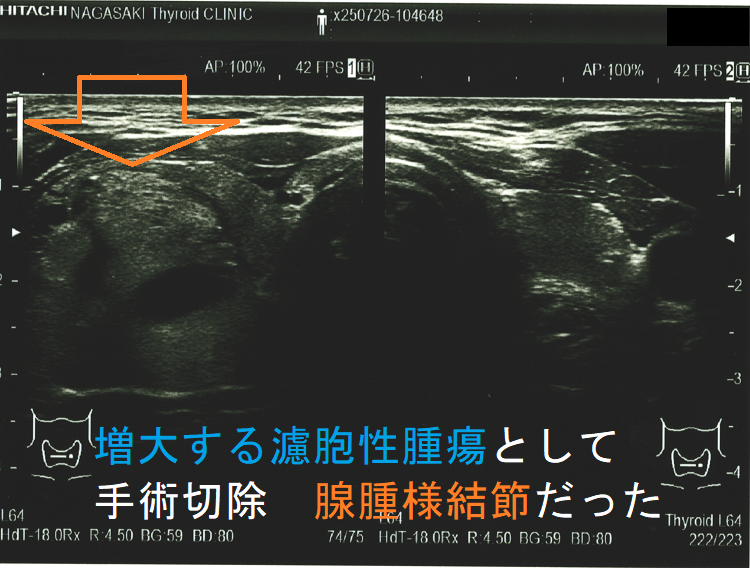

超音波(エコー)画像上、腺腫様結節と甲状腺濾胞性腫瘍は類似しますが

- 被膜があれば甲状腺濾胞性腫瘍ですが、被膜がなければ腺腫様結節[ただし腺腫様結節でも、腫瘍の境界部のハロー(halo:低エコー帯)は、不完全な形で存在します]

- ハローが全周性に認められれば、甲状腺濾胞性腫瘍の可能性が高い。(ただし、ハローの一部途絶、 肥厚等は甲状腺濾胞癌の可能性を考えます。)

- 中心に達する栄養血管がなければ腺腫様結節ですが、あれば甲状腺濾胞性腫瘍・腺腫様結節いずれの可能性もあります。

- 境界の粗雑さは、腺腫様甲状腺腫では0%ですが、良性濾胞腺腫では3.2%です。

- 腺腫様甲状腺腫:14 例(10%);やはり、エコー・細胞診での鑑別が難しいものがありますので